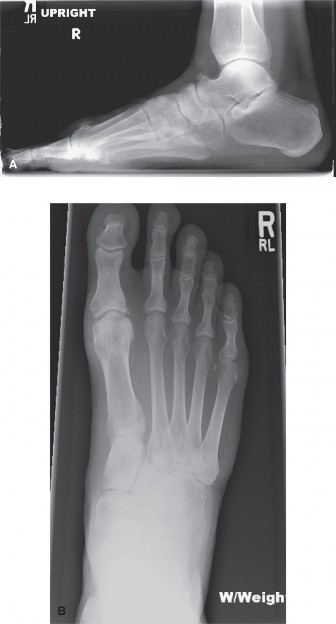

Radiographic Evaluation

Weight-bearing anteroposterior (AP), lateral, and sesamoid axial radiographs are mandatory.

* Evaluate the metatarsal parabola on the AP view to identify an abnormally long metatarsal.

* Assess the lateral view for a plantarflexed metatarsal relative to the adjacent rays.

* Examine the phalangeal heads and bases for hypertrophic condyles or osteophytes contributing to interdigital impingement.

The surgical approach to an IPK is dictated entirely by the specific pathoanatomy identified during the clinical and radiographic evaluation. The goal is to elevate or shorten the offending metatarsal to restore a harmonious weight-bearing distribution across the forefoot.

For a diffuse callosity in which the radiograph demonstrates an abnormally long metatarsal (disrupting the normal cascade where the 2nd metatarsal is longest, followed by the 1st/3rd, 4th, and 5th), a shortening osteotomy is indicated. The Weil osteotomy is the gold standard for this pathology.